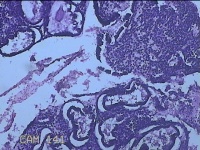

宫腔内容物

性别

女

年龄

41岁

临床诊断

异常子宫出血;取出子宫内节育器;子宫内膜炎

一般病史

阴道不规则流血2个月。

标本名称

大体所见

灰白暗红色不规则碎组织3.5x2.5x0.8cm一堆。